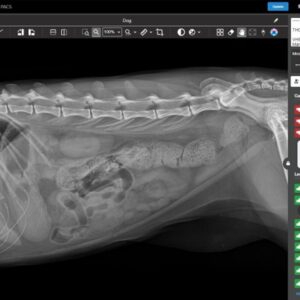

Τα ακτινολογικά μηχανήματα χρησιμοποιούνται ολοένα και περρισσότερο στην κτηνιατρική πράξη . Σήμερα με την χρήση ψηφιακών εμφανιστηρίων είναι ακόμα ευκολώτερη η λειτουργία τους Η επιλογή για αγορά ακτινολογικού μηχανήματος, μπορεί να γίνει ανάμεσα σε διάφορα μοντέλα ανάλογα με τις ανάγκες του κτηνιάτρου Αυτά χωρίζονται βσικά σε απλά και υψίσυχνα (Ηigh Frequency) και σε φορητά ή σταθερά. Σήμερα οι περισσότεροι προτιμούν τα υψίσυχνα τα οποία δίνουν τη δυνατότητα σημαντικής μείωσης των χρόνων έκθεσης λόγω των δυνατοτήτων της υψίσυχνης γεννήτριας παραγωγής ηλεκτρονίων.